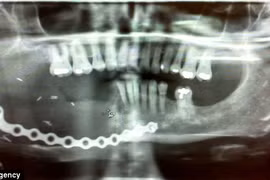

Cấy dây xích vào hàm để thay răng

(Kiến Thức) - Bà Liese 49 tuổi, đã phải ghép một đoạn xích xe đạp vào hàm để có thể trở lại cuộc sống bình thường.